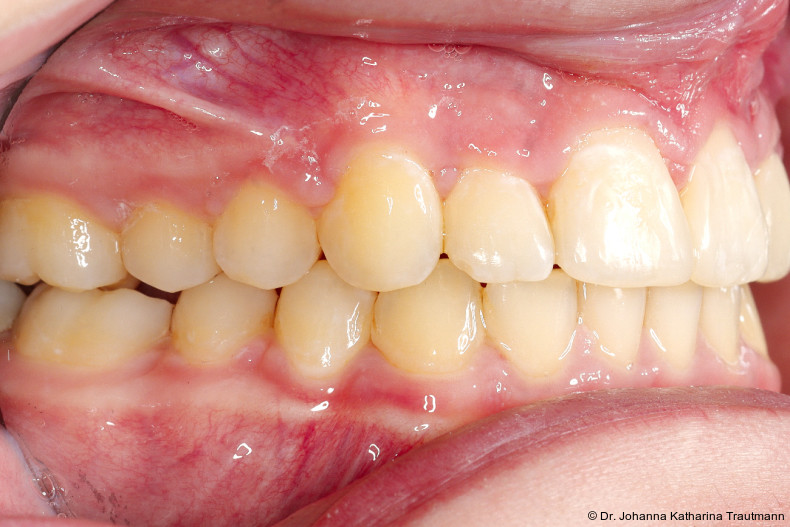

Längere Retentionszeiten ohne odontoplastischen Umbau können das Risiko eines Rezidivs des Zahnes 22 erhöhen. Dennoch ist häufig eine Abheilphase nach der Multibrackettherapie erforderlich, da sich gingivale Entzündungen oft erst nach ein bis drei Monaten vollständig zurückbilden.19–21 Um diesen Zeitraum zu überbrücken wurde an 22 die Kunststoffbasis der DVP (Doppel vorschubplatte) zur Retention sowohl mesial als auch distal extendiert. Schließlich wurden die Zähne 11, 21 und 22 kompositrestaurativ angeglichen, wodurch ein sehr gutes ästhetisches Ergebnis erzielt wer den konnte. Aufbauten mit Komposit bieten eine gute Möglichkeit, bei maximaler Schonung der Zahnhartsubstanz hypoplastische Zähne langfristig zu versorgen, und zeigten in ZehnJahresFollowups hohe Überlebensraten. Entscheidend ist hierbei eine ausgeglichene okklusale Lastverteilung, die mit hilfe einer physiologischen Frontzahnabstützung und gesicherten Okklusion durch die kieferorthopädische Vorbehandlung erreicht werden kann.22

Positiv hervorzuheben ist hingegen der er zielte Knochen erhalt beziehungsweise der partielle Attachmentgewinn im Bereich der Spalte. Wie sich in den Verlaufskontrollen der OPGAufnahmen erkennen lässt, führte die Bewegung der Zähne 21 und 22 in den Spaltbereich zu einer deutlichen Verbesse rung der knöchernen Situation. Obwohl das Knochenniveau nicht vollständig physiologisch ist, konnte ohne zusätzliche Knochenaugmentation eine stabile Knochen und Gewebesituation erreicht werden. Dass ein Attachmentgewinn durch gezielte kieferorthopädische Zahnbewegung möglich ist, wurde bereits von Melsen et al.22 beschrieben. Während sich die meisten nachfolgenden Studien auf parodontal vorgeschädigte Gebisse konzentrierten, zeigt der vorliegende Fall eine mögliche Übertragbarkeit dieser Mechanismen auf Spaltpatienten mit moderatem Knochendefizit.

Zur objektiven Quantifizierung des Behand lungsergebnisses wurde der Peer Assess ment Rating(PAR)Index erhoben.23 Im vorliegenden Fall konnte der PAR-Wert von 25 auf zwei reduziert werden, was einer Verbes serung von 92 Prozent entspricht und als hoch wertiges okklusales Ergebnis einzustufen ist.24 Zur Vorhersage der Langzeitstabilität bei Spalterkrankungen lässt sich dieser Fall in die Gruppe 1 des GOSLON Yardstick Index ein ordnen. Dieser sagt eine exzellente Langzeitstabilität vorher.25 Auch der Patient zeigte sich mit dem Ergebnis sehr zufrieden. Während der anderthalbjährigen Retentionsphase erfolgte zusätzlich eine ästhetische Nasenkorrektur zur Aufrichtung des linken Nasenflügels, wodurch neben der dentalen auch die extraorale Rehabilitation erfolgreich abgeschlossen werden konnte.